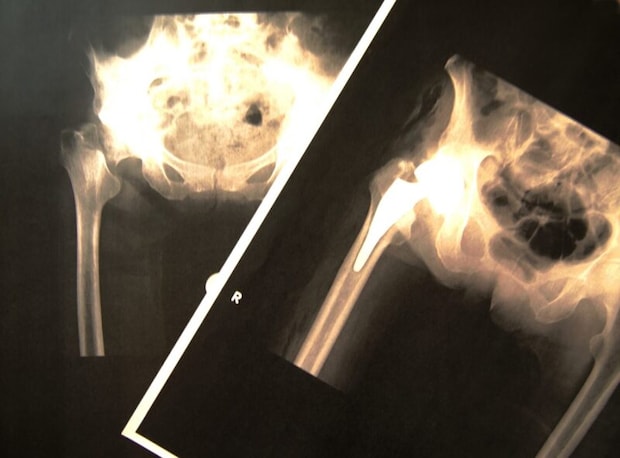

痛みを感じることができなかったせいで、骨折の発見が遅れることもあります。特に折れやすくなるのは手首の骨・背骨・骨盤・肩・太ももの付け根部分の骨です。背中や腰の骨に異常が生じると、2cm以上身長が低くなることもあります。身長が縮むのは椎体が潰れてしまうせいです。その他、背中が丸くなる症状が出ることもよくあります。